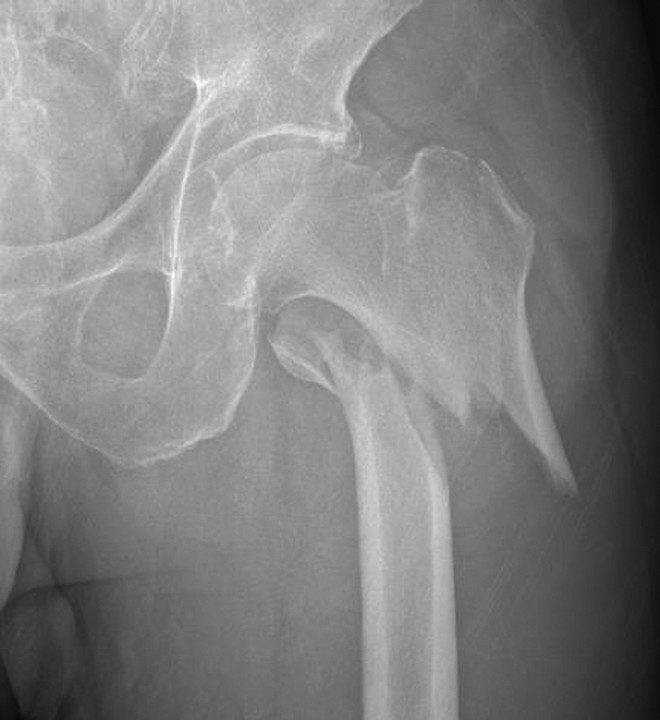

股骨颈内包含抗压与抗拉骨小梁,它们围成Ward三角。该三角上界为抗拉骨小梁,内下界为抗压骨小梁,是骨密度较低的区域(图1)。近期研究表明,骨小梁退化与股骨颈骨折发生密切相关,而Ward三角扩大则与股骨粗隆间骨折相关。

图1. (左)一位30岁女性患者的右髋X光片。(右)一位98岁男性患者的右髋X光片。注意右图中Ward三角(WT)的大小明显大于左图,并且与左图相比,右图中主要抗压骨小梁(A)和主要抗拉骨小梁(B)的退变更明显。